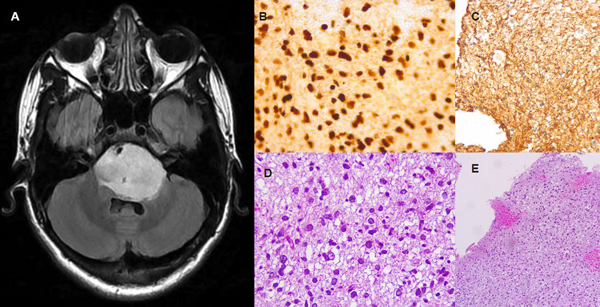

Al ingreso se realizó una Resonancia Magnética Nuclear (RMN) en donde se evidencia una lesión pontina expansiva e infiltrativa de 48mm de diámetro máximo, hipointensa en T1 e hiperintensa en FLAIR/T2, con nódulo en su interior que realza con contraste EV. La lesión presentaba expansión hacia el 4to ventrículo, ambos ángulos pontocerebelosos y mesencéfalo a izquierda (Fig. 1A). Se completó estudios con RMN de columna completa, que no evidenció signos de metástasis.

Se colocó una válvula de derivación ventrículo peritoneal previo a la intervención quirúrgica. Posteriormente se realizó la biopsia quirúrgica a cielo abierto mediante un abordaje subtemporal, de la cual se enviaron a patología 3 fragmentos de 2 cm x 1 cm. La anatomía patológica informó glioma difuso de línea media H3 K27M mutado (grado 4 de la OMS). (Fig. 1B-E). El paciente cursó 3 días de internación en unidad de terapia intensiva y 2 días en sala general, donde fue otorgado el egreso sanatorial por buena evolución. No presentó complicaciones ni intercurrencias. Actualmente se encuentra realizando tratamiento oncológico dirigido. (Fig. 2)

Fig 1: Caso 1.: A. Secuencia FLAIR de RMN diagnóstica prequirúrgica, en donde se evidencia lesión difusa pontina, hiperintensa, que genera compresión y desplazamiento del IV ventrículo. B,C,D y E. Cortes histológicos de los resultados patológicos, evidencian tinciones de GFAP y hematoxilina-eosina, con proliferación neoplásica, núcleos ovalados y moderado pleomorfismo. Sin signos de proliferación vascular ni necrosis. Con tinción positiva para H3K27M (B) y GFAP (C), compatibles con diagnóstico de glioma difuso de línea media.